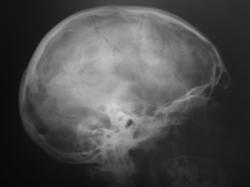

Пациент в ургентном порядке, после ДТП был доставлен в ЦРБ в ночное время. Был вызван "ургентный лаборант" для рентгенографии черепа. Пациент без сознания. С учетом состояния пациента рентгенография произведена в нестандартных проекциях - "задняя прямая".

Линейный перелом костей крыши черепа, возможно с переходом на основание. Вот только не понятно есть или нет импрессионный перелом височной кости, а ещё больше похоже на наличие пневмоцефалии.

А что скажите по поводу пирамидки и орбиты справа?

Контуры пирамиды чёткие, а вот латеральная стенка орбиты возможно сломана. Он был отправлен в ОКБ?

Он в реанимации - нетранспортабилен.

Линейный перелом с переходом на основание - дно средней черепной ямки. Сейчас вопрос о пирамидке и орбите не принципиальный. Главный вопрос нет ли внутричерпной гематомы. Если больной выйдет из тяжелого состояние, и встанут экспертные вопросы можно сделать Стенверс при потере слуха, Майер при кровотечении из уха. Насчет стенки орбиты - наличие перелома сомнительно, явно не видно. Также можно доснять при улучшении состояния. Судя по всему это молодой человек. Сколько лет?

Вижу только линию перелома височной и теменной костей, высока вероятность перехода на основание, остальное - домыслы и сомнения.